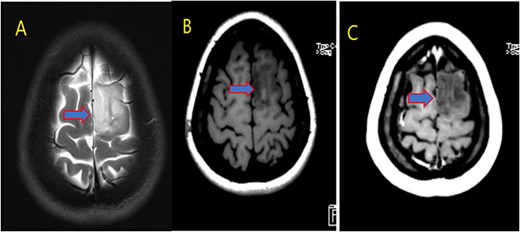

Our patient is a 31-year-old female who presented to the emergency department due to two episodes of generalized tonic colonic seizures. Upon presentation, the patient was administered with supplemental oxygen. She was drowsy and confused while exhibiting signs of right-sided hemiparesis and paralysis. Her pupils were 3 mm and reacted briskly while she showed good left-sided localizing. Her seizures terminated after intravenous administration of midazolam at 5 mg. Further, it was known that she has been symptomatic for 1 month and had been suffering from episodes of seizures, with shaking and tremors of upper limbs, and brief episodes of blackouts for about a minute. These episodes were associated with headache and nausea but were self-limited. Seizures recurred two to three times per week. She denied any fall, tongue bite, loss of consciousness, and limb weakness or numbness. A computerized tomography (CT) scan was suggested, which showed left high parietal hypodensity with vasogenic edema (Fig. 1). She was recommended Keppra 1.5 g and dexamethasone 12 mg. Further, a contrast MRI of the brain was performed (Fig. 2). After a thorough evaluation of the patient’s medical records and current condition, it was decided to proceed with an excision of the tumor using the AC technique. To foster trust and comfort, the same anesthesia and surgical teams were assigned to the patient. Before the procedure, the patient was fully informed about the nature of the procedure and the possibility of a failed outcome or further need for a conversion to general anesthesia. To assess the patient’s cognitive and language abilities, preagreed questions and exercises were performed. These included memory-related queries, such as asking for the patient’s phone number and the names of her dog, and motor commands, such as squeezing a squeaky toy. The patient was prepared for awake navigator-assisted left frontal craniotomy for excision of the left frontal lobe space-occupying lesion, which was suspected to be either a low-grade glioma or fibrous dysplasia. During the surgical procedure, a central line was placed in the right jugular vein using ultrasound, followed by the insertion of a right radial arterial line, a urinary catheter, and two additional venous lines. The patient received a continuous flow of 4–6 l of oxygen per minute. To achieve conscious sedation, the patient received infusions of remifentanil and propofol at varying rates. The patient underwent a 5-hour surgical procedure to remove a tumor. During the procedure, the patient was under sedation and was regularly tested for response to predetermined commands. Her conscious sedation level fluctuated, but she never lost consciousness. The removal of the tumor was successful, and postoperative examination revealed normal motor function and cranial nerve function. The patient was taken to the intensive care unit, and postoperative MRI showed a reduction in the size of the mass lesion in the left frontal lobe/superior frontal gyrus along with mild vasogenic edema surrounding it (Fig. 3).

MRI brain with contrast; (A) T2, (B) T1, and (C) T1 post contrast; space occupying cortical mass lesion in the left frontal lobe/superior frontal gyrus showing mild faint minimal contrast enhancement (C) (low-grade glioma).